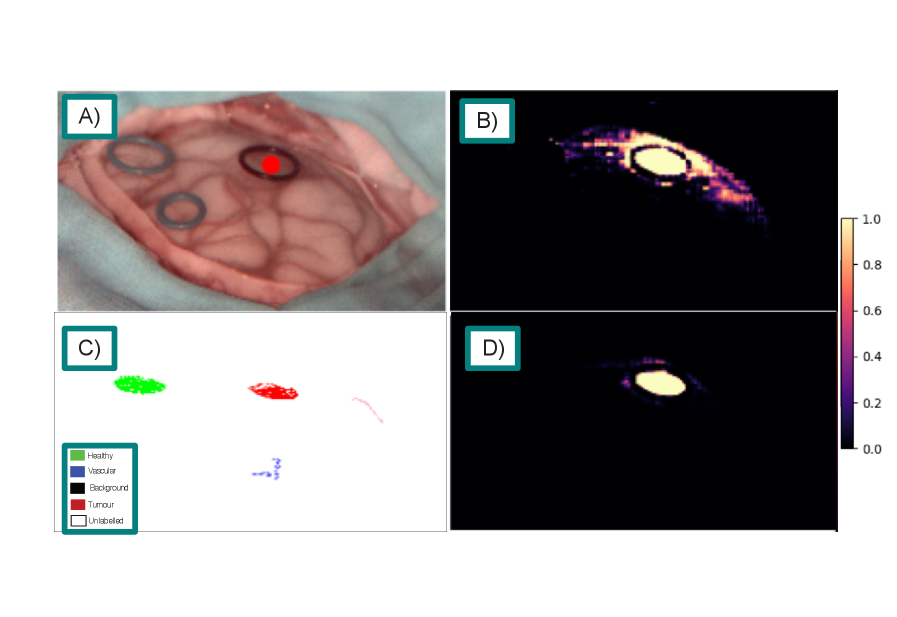

Qualitative comparisons further highlight the advantages of SAMSA2 over fine-tuned RGB baselines. On the HIB dataset (fig. 2), both SAMSA2-Large and SAM2-Large-FT correctly localise the tumour, but SAMSA2 provides a more refined boundary, offering greater clinical interpretability. On the SB-X and SB-H datasets (figs. 3 and 4), both methods capture the tumour within the marked region, yet SAMSA2 extends its prediction beyond the visible margins, suggesting the potential to reveal subsurface infiltration that may not be apparent in RGB-based predictions alone. For the HEIPOR dataset (fig. 5), performance is broadly comparable, though SAMSA2 produces fewer false positives, avoiding spurious activations in neighbouring tissue seen with SAM2-Large-FT. Finally, fig. 6 illustrates a representative workflow with SAMSA2-Large: tumour prompts reveal infiltration extending beyond the visible tumour boundary, while healthy prompts delineate the transition from normal to abnormal tissue. This bidirectional prompting demonstrates how SAMSA2 could support decision-making by helping identify resection margins more precisely.

Refer to caption

Figure 4: Sample segmentation results on the SB-H dataset, tumour class. A) Pseudo-RGB image of the target. B) SAMSA2-Large standard predicted similarity. C) Ground truth labels. D) SAM2-Large-FT using SAM2 predicted similarity